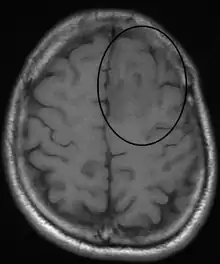

An oligodendroglioma as seen on MRI

Oligodendrogliomas are generally felt to be incurable using current treatments. However compared to the more common astrocytomas, they are slowly growing with prolonged survival. In one series, median survival times for oligodendrogliomas were 11.6 years for grade II.[11]